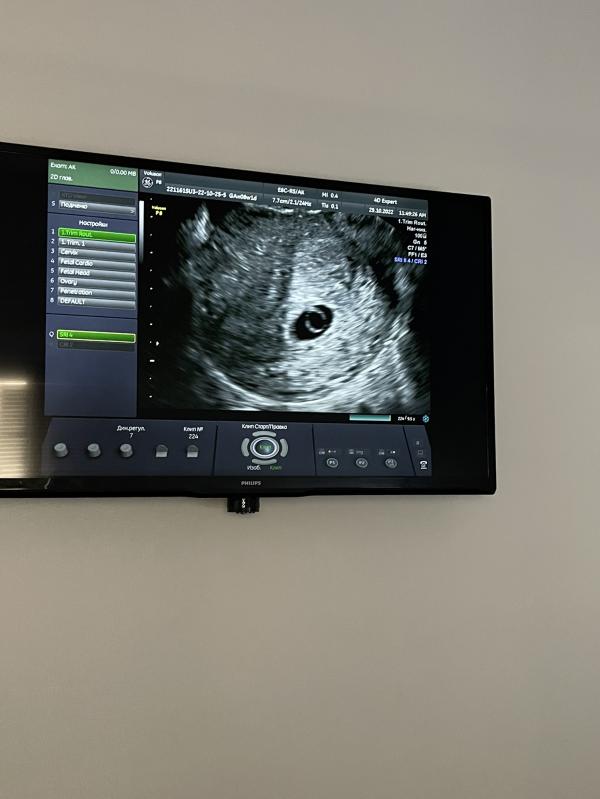

Девочкииии божечки 😭😭😭😭! Вот моя крошечка ❤️!

Пульсация сердечка слабая ! 5 недель 6 дней срок по узи . У кого так было 😭боюсь немного ….